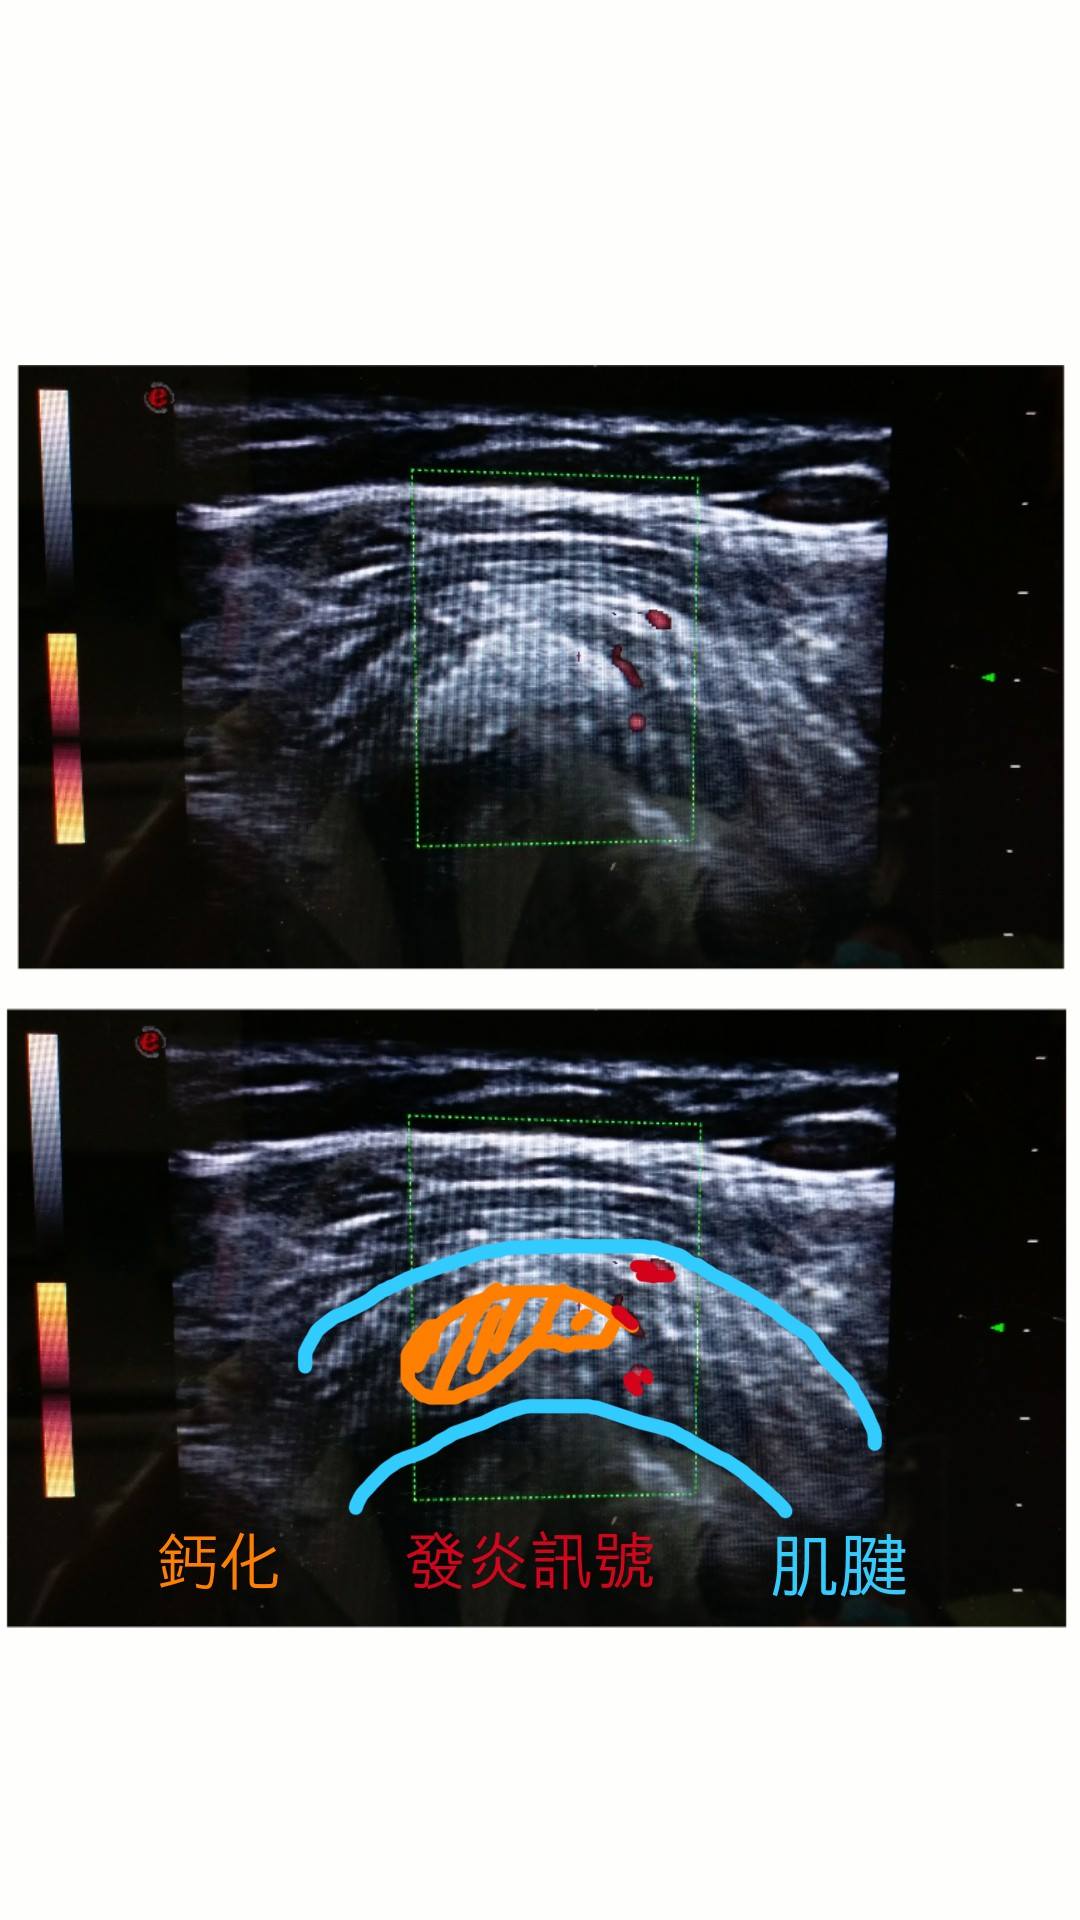

↑超音波下,急性發炎中的鈣化

在“超音波導引”之下,將消炎藥物直接注射到發炎的位置,可以快速有效降低發炎和疼痛。